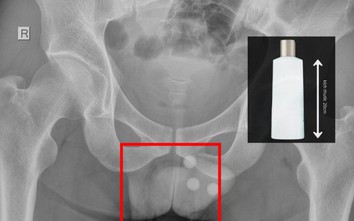

Chai nhựa dài 20cm mắc kẹt trong trực tràng người đàn ông, bác sĩ cảnh báo biến chứng nguy hiểm

Dân số và phát triển

GĐXH - Một người đàn ông nhập viện trong tình trạng đau rát dữ dội vùng hậu môn. Qua thăm khám, bác sĩ phát hiện một chai nhựa dài khoảng 20cm mắc kẹt sâu trong trực tràng.